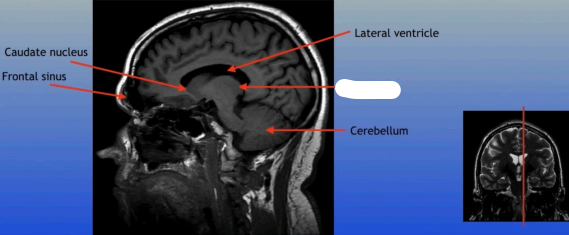

Caudate Nucleus

A C-shaped structure within the brain's basal ganglia, involved in various functions including motor control and learning.

Frontal Sinus

A paired cavity located within the frontal bone, above the eyes, that plays a role in sinus drainage and resonance of the voice.

Lateral Ventricle

A fluid-filled cavity located within each hemisphere of the brain, part of the ventricular system, that helps cushion the brain and circulate cerebrospinal fluid.

Cerebellum

A large structure located at the back of the brain responsible for coordination, balance, and fine motor control.